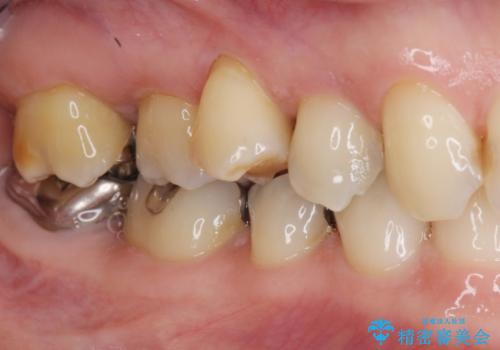

部分矯正を含む 歯周病治療 (再生治療・歯周ポケット除去・MTM・連結補綴)

- 75万円(仮歯・メタルボンドクラウン×3・再生療法・小矯正・歯周ポケット除去手術)費用は治療当時の料金となります

今回連結補綴を行うにあたり、歯周病の問題を解決するために再生療法・歯周ポケット除去手術を、またより歯の神経を保存し力に対抗できる環境を整えるために小矯正を行い精度の高いメタルボンドクラウンを製作することができました。